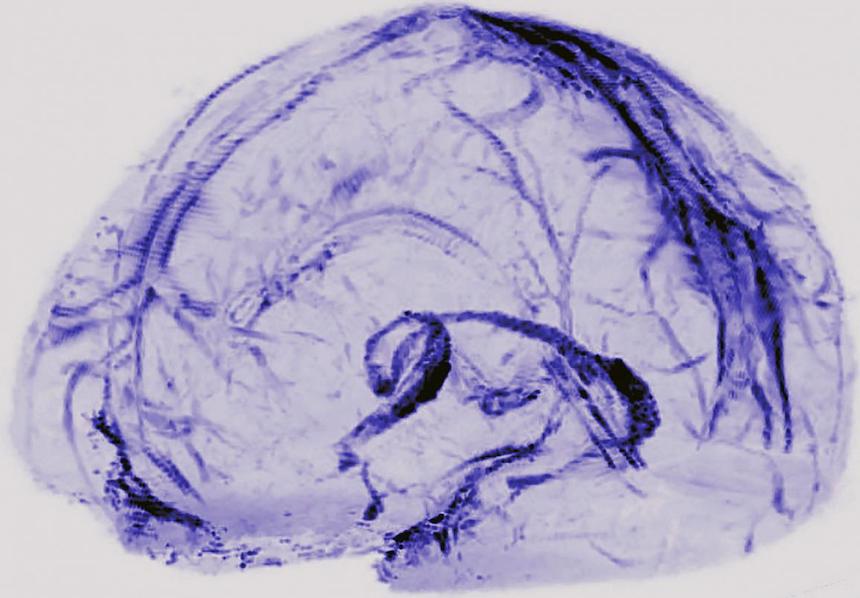

To look for the vessels, Dr. Reich’s team used MRI to scan the brains of five healthy volunteers who had been injected with gadobutrol, a magnetic dye typically used to visualize brain blood vessels damaged by diseases, such as multiple sclerosis or cancer. The dye molecules are small enough to leak out of blood vessels in the dura but too big to pass through the blood-brain barrier and enter other parts of the brain.

At first, when the researchers set the MRI to see blood vessels, the dura lit up brightly, and they could not see any signs of the lymphatic system. But, when they tuned the scanner differently, the blood vessels disappeared, and the researchers saw that dura also contained smaller but almost equally bright spots and lines which they suspected were lymph vessels. The results suggested that the dye leaked out of the blood vessels, flowed through the dura and into neighboring lymphatic vessels.

To test this idea, the researchers performed another round of scans on two subjects after first injecting them with a second dye made up of larger molecules that leak much less out of blood vessels. In contrast with the first round of scans, the researchers saw blood vessels in the dura but no lymph vessels regardless of how they tuned the scanner, confirming their suspicions.